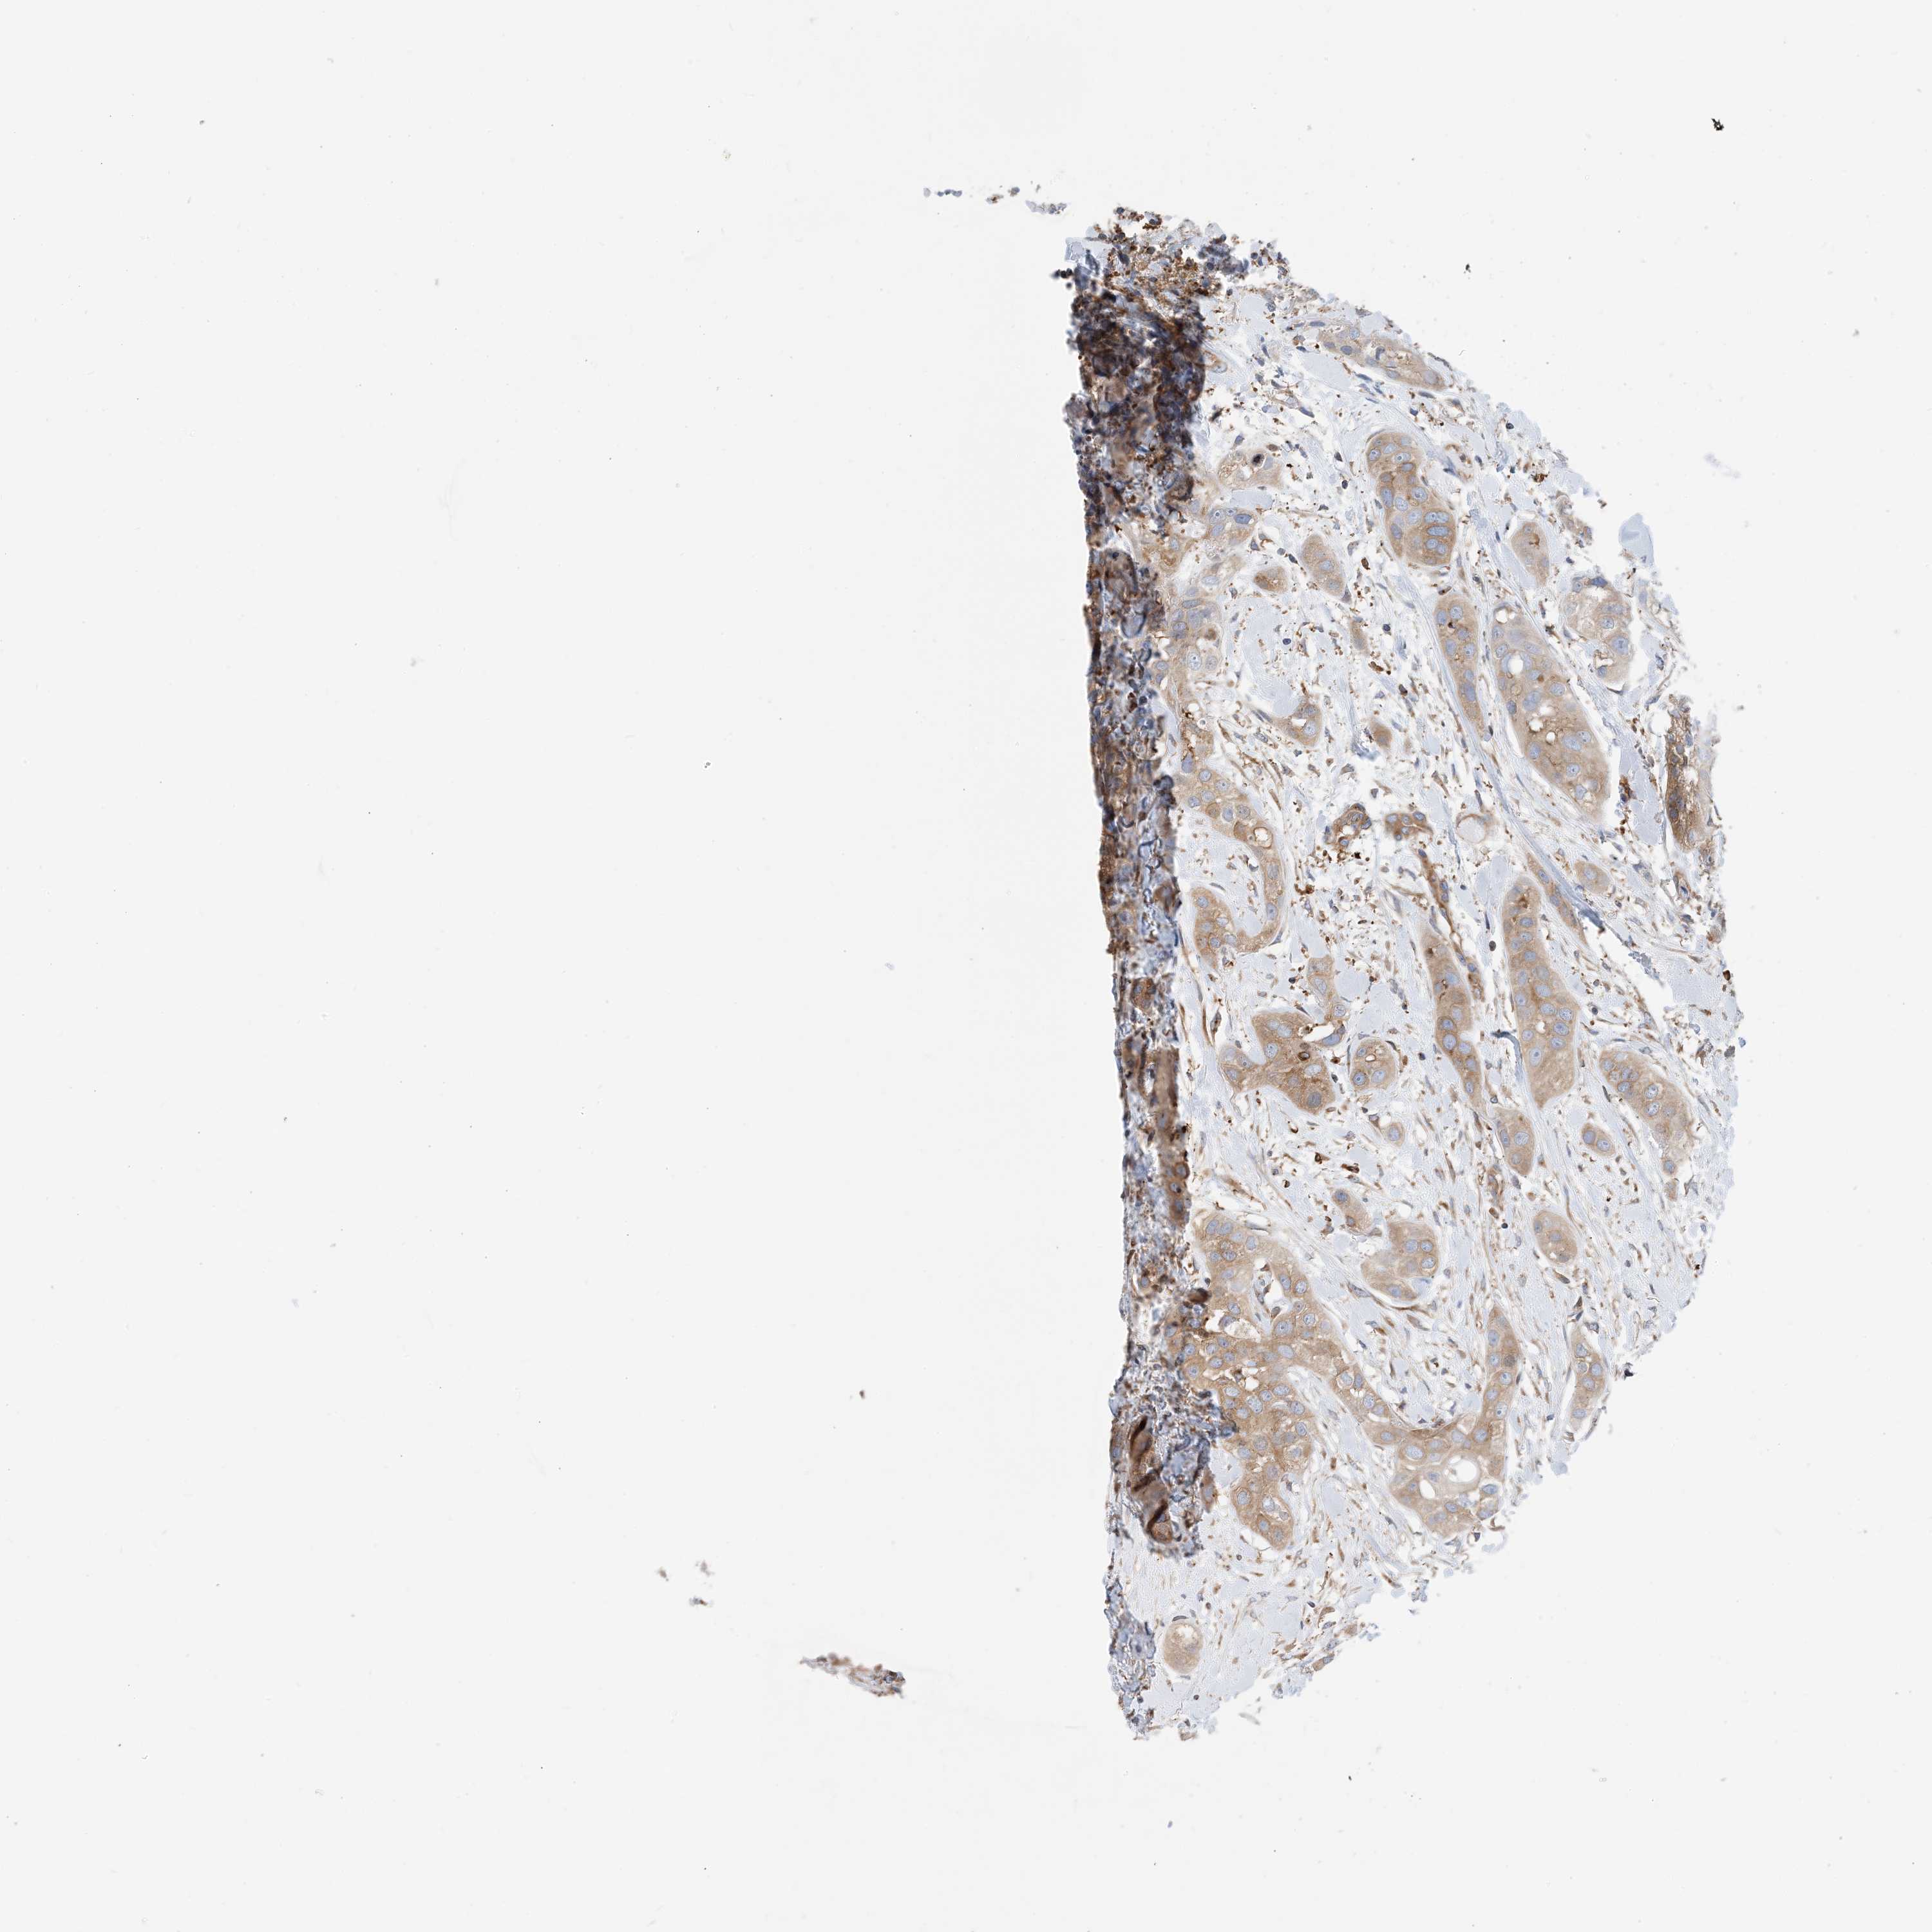

HEAD AND NECK CANCER - Protein expressioni

A mouse-over function shows sample information and annotation data. Click on an image to view it in a full screen mode. Samples can be filtered based on level of antibody staining by selecting one or several of the following categories: high, medium, low and not detected. The assay and annotation is described here.

Antibody stainingi

Antibody staining in the annotated cell types in the current human tissue is reported as not detected, low, medium, or high, based on conventional immunohistochemistry profiling in selected tissues. This score is based on the combination of the staining intensity and fraction of stained cells.

Each image is clickable and will lead to virtual microscopy that enables deeper exploration of all samples and also displays staining intensity scores, fraction scores and subcellular localization as well as patient and tissue information for each sample.

Antibody HPA035013

Squamous cell carcinoma, NOS

Squamous cell carcinoma, metastatic, NOS

Adenocarcinoma, NOS